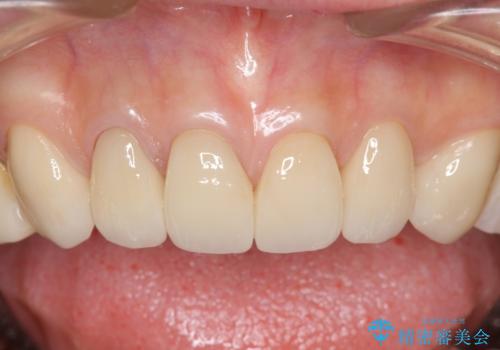

4年半前のクラウン装着時と変わらず、まるで天然歯のように自然に見えました。

患者様の良好なセルフケアと精密な適合の良いクラウンにより、歯肉の腫脹や退縮も認められませんでした。

4年半前に行った治療に大変ご満足頂き、他の部位の治療のため再来院して下さいました。